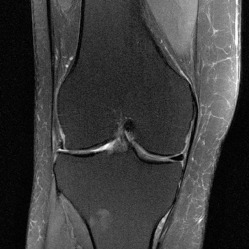

fastMRI 核磁共振成像数据集,是一个原始 MR 测量与 MR 图像的大型集合。该数据集包括了 膝关节 MRI 与大脑(神经)MRI,由训练集、验证集和掩盖测试集构成,主要可用于训练与评估 MR 图像重建的机器学习方法,同时也为缺乏医学成像背景的机器学习研究者,提供相应背景知识的介绍。